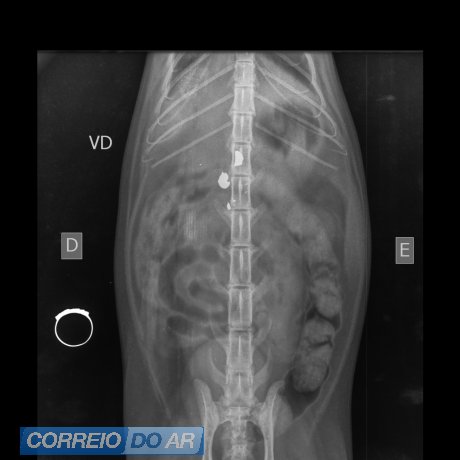

O animal apresentava um ferimento compatível com projétil. Não foi possível confirmar se o disparo partiu de arma de fogo ou de pressão. A gata foi socorrida e encaminhada para atendimento veterinário.